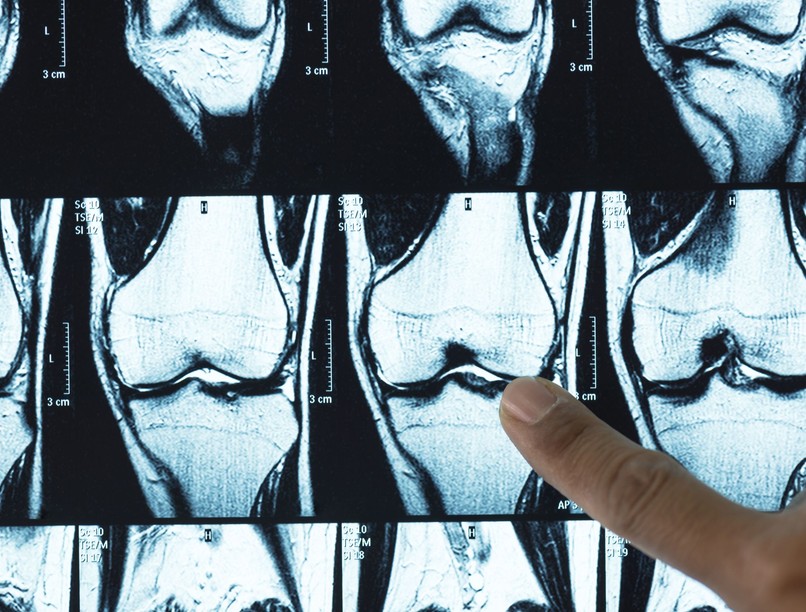

A porc leépülése az osteoarthritis egyik legfájdalmasabb és leginkább életminőséget rontó folyamata. Most azonban egy új kutatás reményt adhat: a Stanford Egyetem tudósai olyan biológiai mechanizmust azonosítottak, amely megmagyarázhatja, miért pusztul a porcszövet, és hogyan lehet azt regenerálni. Egy kísérleti gyógyszer egereken már képes volt visszafordítani az osteoarthritis folyamatát – ami, ha embereknél is beválik, történelmi mérföldkövet jelenthet.

A Science folyóiratban megjelent tanulmány szerint az öregedéssel összefüggő 15-PGDH nevű fehérje felhalmozódik az osteoarthritises ízületekben. Ez a fehérje lebontja azokat a prosztaglandin-molekulákat, amelyek nélkülözhetetlenek a szövetek regenerációjához. A kutatók egy olyan kísérleti készítményt teszteltek, amely blokkolja a fehérje működését – az eredmények pedig egészen figyelemreméltóak.

A gyógyszert először térdízületi osteoarthritisben szenvedő egereken próbálták ki. A kezelés jelentősen javította a porc vastagságát és minőségét, visszaadta az ízület terhelhetőségét, és csökkentette a fájdalomra utaló jeleket. Amikor a kutatók emberi – műtétek során eltávolított – porcszöveten is tesztelték, ott is szövetregenerációt figyeltek meg.

Az osteoarthritis nem „egyszerű” porckopás, hanem egy összetett biológiai folyamat. Az ízületek felszínét egy rendkívül ellenálló, sima, rugalmas szövet borítja: ez a hialinporc, amely olyan, mint egy tökéletesen olajozott csúszófelület. Ennek köszönhető, hogy a csontok terhelés közben sem súrlódnak egymáshoz.

Ahogy azonban öregszünk, a porc víztartalma csökken, rugalmatlanná válik, mikrosérülések jelennek meg rajta. A szervezet erre gyulladással reagál, amely tovább gyorsítja a szövet pusztulását. A porc elvékonyodik, végül akár teljesen eltűnhet.

Miért olyan nehéz visszaépíteni a porcot?

A hialinporc sajátossága, hogy gyakorlatilag nem tartalmaz ereket. Ez azt jelenti, hogy: